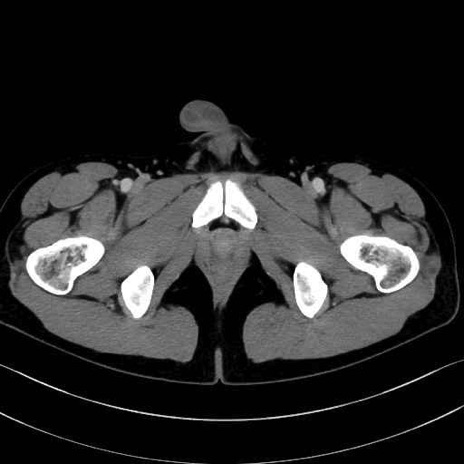

梨状筋(piriformis muscle) のCT画像の解剖

梨状筋 (Piriformis)

内閉鎖筋 (Obturator internus)

外閉鎖筋 (Obturator externus)